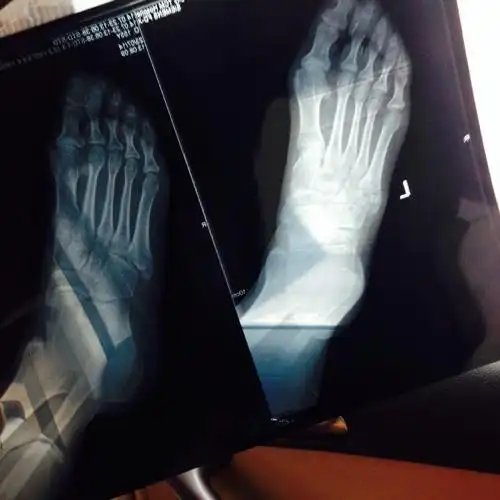

x 射线,脚,骨

脚掌骨折拆石膏后多久可以正常行走 2010-08-18 为什麽骨折的人石膏拿

第一跖趾关节也就是足大拇指与脚掌的第一跖骨形成的关节,为了方便筋

足骨骨折多久能好